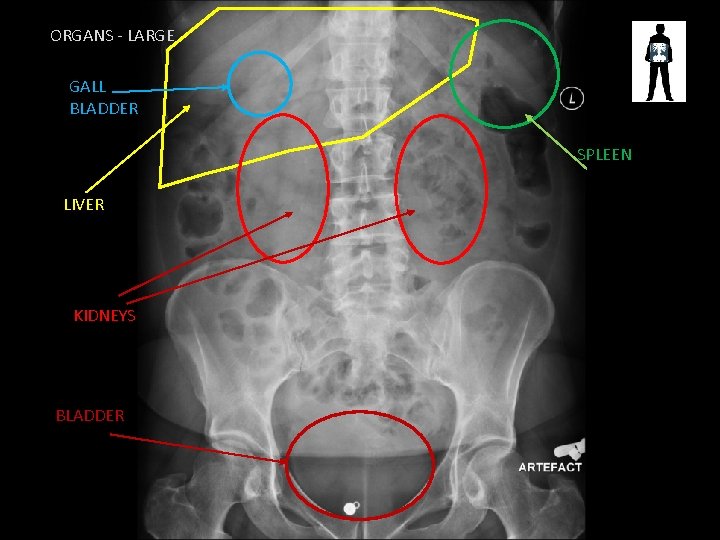

ORGANS - LARGE GALL BLADDER SPLEEN LIVER KIDNEYS BLADDER